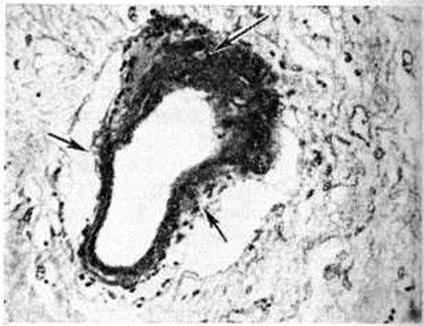

Микропрепараты ткани головного мозга: 1 — нормальная структура сосудистой стенки артерий малого и среднего калибра в подкорковых узлах головного мозга человека (дано для сравнения); × 400; 2 — плазматическое пропитывание стенки мелкой артерии (указано стрелками) б подкорковых узлах; × 200. Окраска гематоксилин-эозином.